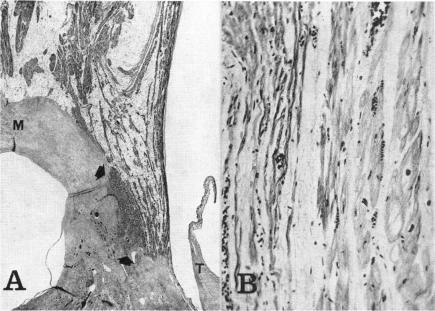

Cardiac innervation: anatomic and pharmacologic relations.

Bull N Y Acad Med. 1967 Dec;43(12):1041-86.